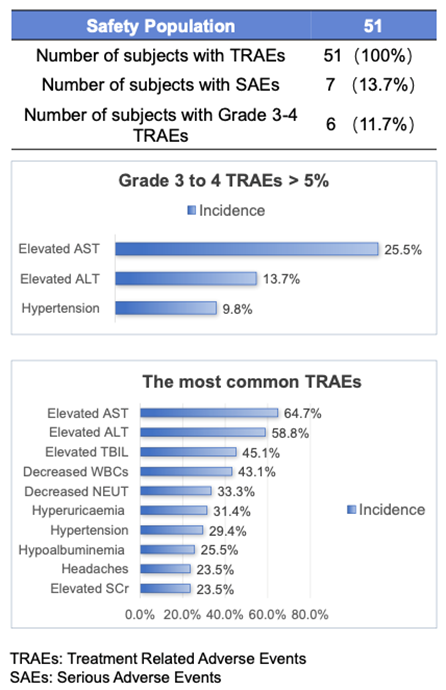

安全护航:BYS10治疗RET突变实体瘤安全性良好

所有受试者均出现治疗相关不良事件(TRAE),最常见的TRAE为AST升高(64.7%)���、ALT升高(58.8%)、TBIL升高(45.1%)��、WBC降低(43.1%)��、NEUT降低(33.3%)��、高尿酸血症(31.4%)����、高血压(29.4%)����、低白蛋白血症(25.5%)、SCr升高(23.5%)和头痛(23.5%)[1]����。

BYS10的暴露量以剂量依赖性的方式从25mg增加到600mg��。其中,100 ~ 300 mg BID组报告的3 ~ 4级TRAE(>5%)包括AST升高(25.5%)���、ALT升高(13.7%)和高血压(9.8%)��。严重不良事件7例[1]���。

图2.安全性结果